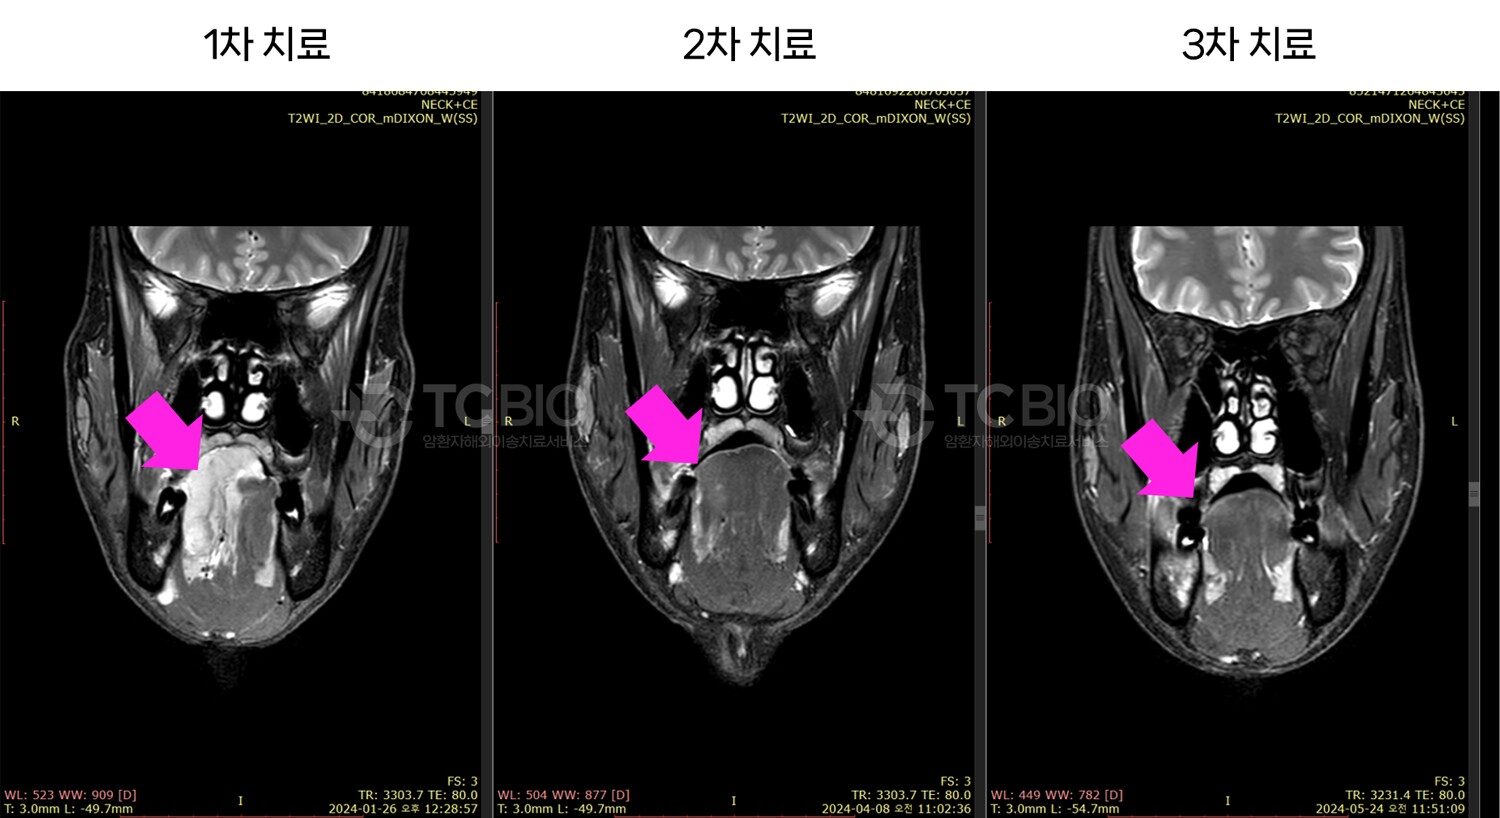

IVR 치료(Interventional Radiology)는 국내에서 흔히 색전술로 알려져 있는 TACE(Transarterial Chemoembolization) 치료의 더 진화한 형태로, C-ARM을 이용하여 투시, 혈관 조영, 초음파, CT 등의 이미지를 동시에 보면서 체내에 얇은 관(카테터)를 이용하여 종양에 항암제를 직접 넣어 치료하는 방식입니다.

IGT클리닉에서의 IVR치료는 기존 TACE 치료의 방식과 내용이 확실히 다릅니다.